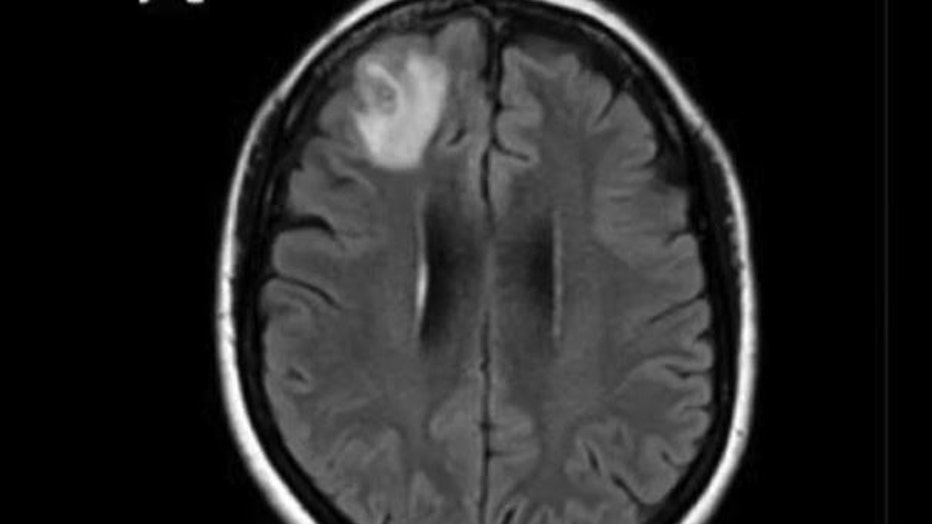

The woman had been admitted to the hospital after experiencing forgetfulness and worsening depression over three months. Scans showed changes in her brain.

Senanayake said the brain biopsy was expected to reveal a cancer or an abscess.

"This patient had been treated ... for what was a mystery illness that we thought ultimately was a immunological condition because we hadn’t been able to find a parasite before and then out of nowhere, this big lump appeared in the frontal part of her brain," Senanayake said.